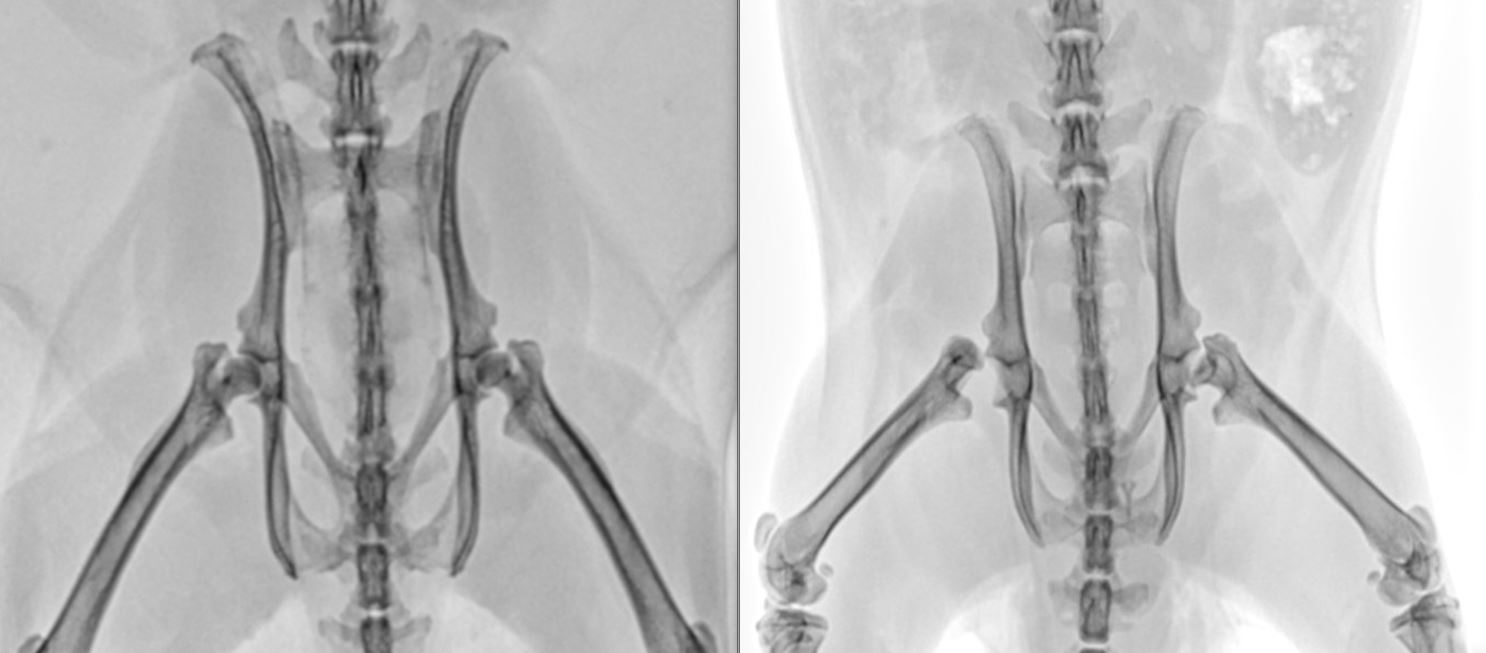

Bei Rudi könnte man meinen, dass die Hüftgelenke nicht (mehr)

vorhanden sind. Er gleicht Instabilität mit seinem Schwanz aus.

Vergleich: links Hüfte ok- rechts Hüfte Rudi